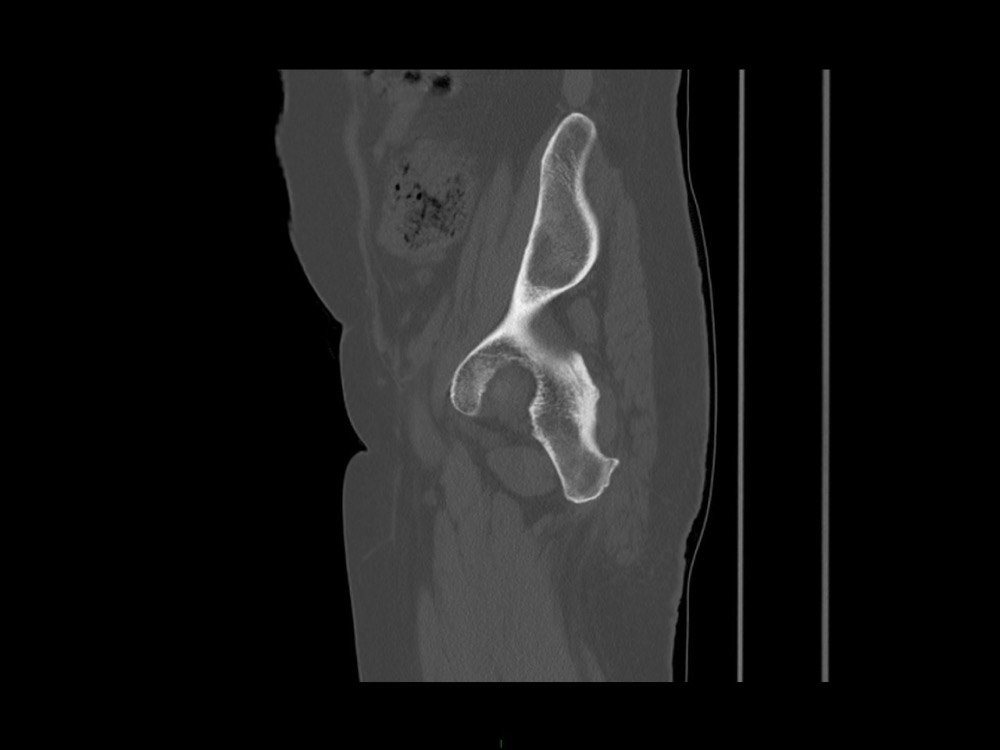

Aboudaram / Burns 11/01/2023